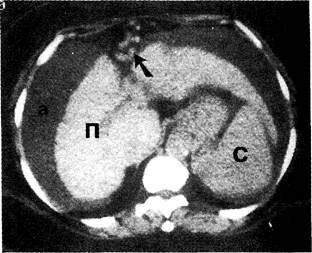

КТ ретроперитонеального фиброза: Изображения и диагностика

Раздел: Мудрость в деталях